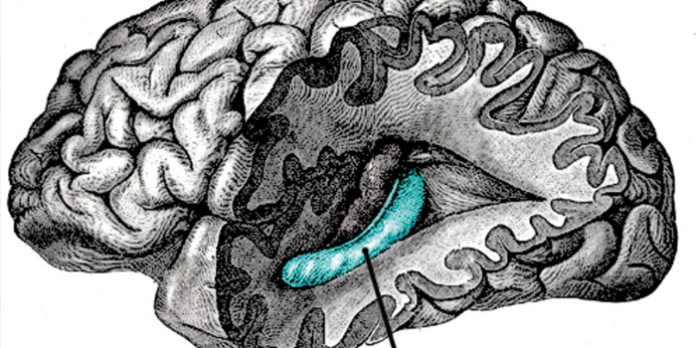

En concreto, Larry R. Squire, PhD, un científico de Carrera del Investigador en el Centro Médico VA, San Diego y profesor de psiquiatría, las neurociencias y la psicología en la Universidad de San Diego, y Christine N. Smith, PhD, científico del proyecto, dice que, contrariamente con las ideas actuales en el hipocampo (una pequeña estructura con forma de caballito de mar, ubicado en la profundidad en el centro del cerebro y largo plazo asociados con la función de memoria) es compatible con el recuerdo y la familiaridad recuerdos cuando estos recuerdos son muy fuertes.

Prevalece la investigación postula que la memoria el recuerdo y el conocimiento a regiones diferentes en el lóbulo temporal medial del cerebro: el hipocampo para el recogimiento, la corteza adyacente perirrinal de familiaridad.

No es sorprendente que los elementos habían recogido una mayor precisión y clasificación de confianza entre los participantes que hicieron cosas familiares. Estudios previos han producido resultados similares. Sin embargo, cuando la Universidad de California en San Diego en comparación recordó los científicos y los objetos familiaresque fueron muy recordado, los datos mostraron que el hipocampo participa activamente en dos, a diferencia deestudios anteriores.

En el segundo, Squire, con el co-autores canción Zhuang, PhD, un investigador postdoctoral, y Annette Jeneson,un estudiante de posgrado, que se utiliza una combinación nueva de neuroimagen con otras pruebas para demostrar también que el hipocampo está relacionado con la codificación del conocimiento-las memorias basadas tema, los recuerdos no sólo basada en el recuerdo.